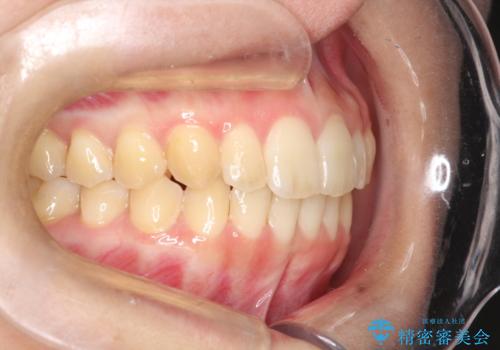

出ている前歯をインビザラインにて引っ込める

- 前歯が少し前に出ているのが気になるとのことで来院されました。

インビザラインにて上顎の歯を全体的に後方に移動させて前歯を引っ込める計画としました。

使用時間を守っていただけたので、比較的スムーズに矯正を終了することができました。